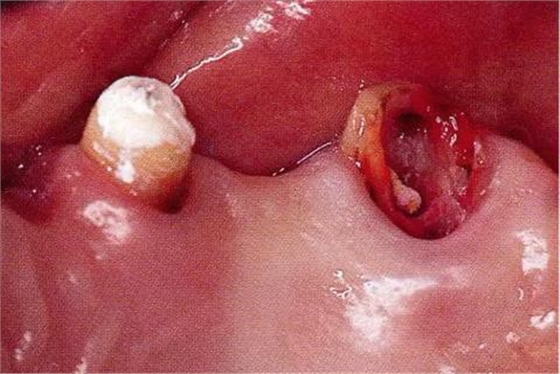

▼圖16-4

圖16-4進(jìn)行牙齒分割時(shí),如圖所示一樣,要確保分割去除的牙根邊緣不會(huì)殘留在牙槽中間骨脊。如果有邊緣殘留,會(huì)造成軟組織發(fā)紅,引發(fā)炎癥。

▼圖17

圖17將右上6近中頰側(cè)根拔除,考慮到修復(fù)物清潔性的情況下進(jìn)行備牙。牙齒分割后如果有邊緣殘留,就會(huì)使切割面的牙齦發(fā)紅無(wú)法治愈。